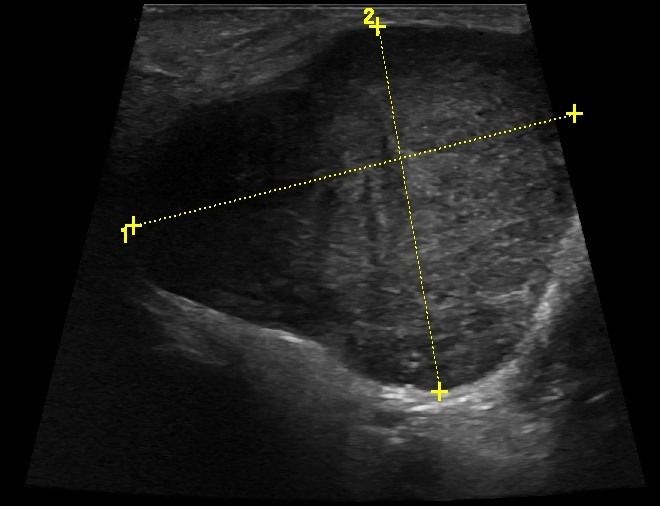

- Διάταση των εκφορητικών πόρων και εντοπισμό λίθων στα πλαίσια σιελολιθίασης και σιελαδενίτιδας

- Εστιακές βλάβες, όπως όγκοι (πλειόμορφο αδένωμα, όγκος Warthin, λέμφωμα)